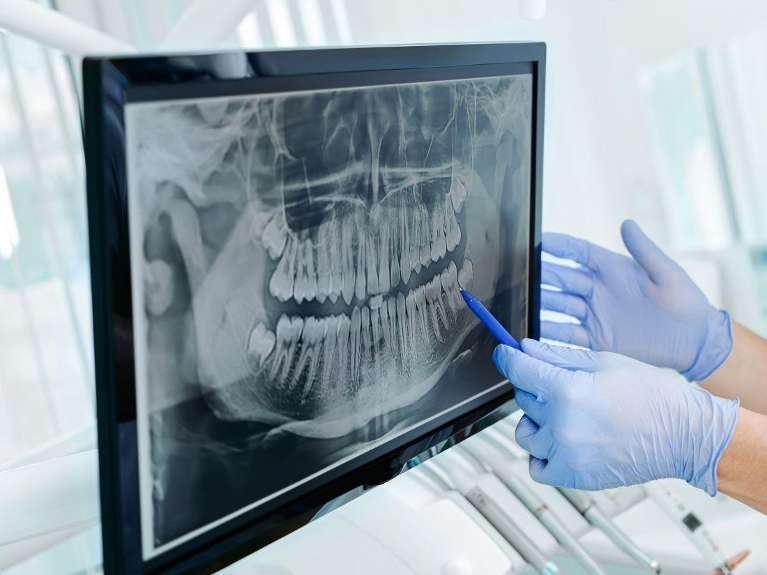

Panoramic X-Rays

Individual x-rays are beneficial for identifying decay, infection, and many other dental conditions. Having a full-picture view is often helpful, and that’s where panoramic x-rays come in handy. Panoramic x-rays take a full-picture view of the teeth, bone, jaw joints, and other biological landmarks. These types of x-rays are helpful in planning oral surgeries, such as extractions and dental implant placement, as well as identifying tumors, cysts, and jaw joint problems.